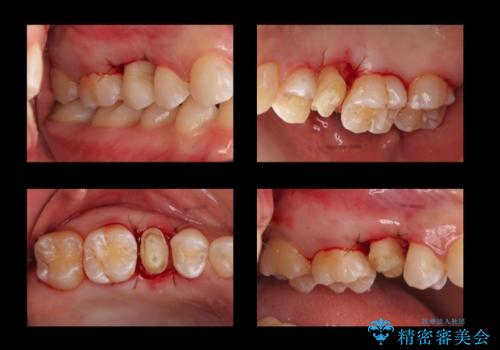

高さがなく外れやすいことに関しては、高さを出す以外にないのですが、向かい合わせの歯があるため、被せ物の高さを高くするわけにいきません。

また、骨の高さを変えずに歯肉の奥深くまで削ると、歯肉の炎症になってしまいます。慢性的な炎症となり、すぐ出血するような状態が治らなくなってしまいます。

そうなると正確な歯型が取れなくなり、被せ物と歯の間に隙間が生じ、虫歯のリスクが飛躍的に高まります。歯肉の奥深くに隙間があるような状態は歯ブラシができないので悪化の一途をたどってしまいます。